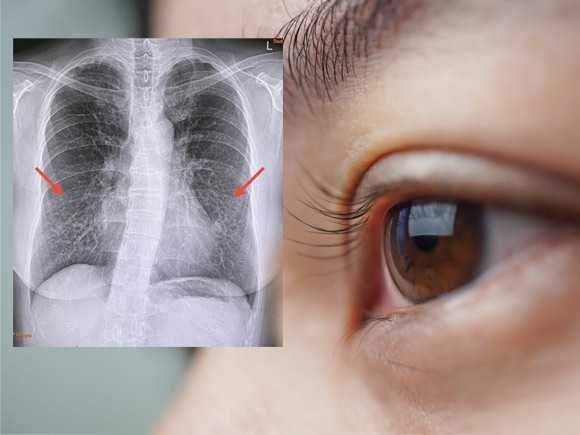

มะเร็งปอด